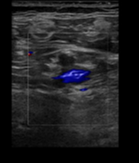

Hallazgos ecográficos

Ecografía clínica en el mismo momento de la consulta: vena poplítea derecha y vena safena derecha no compresibles imagen hipoecocicas sugestivas de tombo sugiere trombosis venosa profunda en territorio poplíteo. Se deriva a hospital.

Ecografía diagnóstica Doppler de confirmación en hospital: trombosis venosa profunda poplítea derecha.